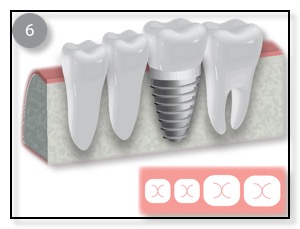

There are two basic types of bone grafting for dental implants. The most common one is after you have a tooth extracted, or if you lost a tooth awhile back. There could be insufficient bone support in such scenarios and thus a bone graft is needed. (See diagram above.) Dr. Tsai will numb the gum before making an incision to expose the area requiring the graft, or if the tooth was just extracted, then she will gently push the gum back to expose the existing bone. She will then place the graft, anchoring it in place if necessary, before covering it with a membrane and suturing the gum back in place. You will be given instructions on how to care for the bone graft site, and how to keep it clean. Bone grafts generally need to be left to heal for several months, although, if the amount of bone grafted was relatively small, it may be possible to place the implant at the same time.

Once the bone is heal, Dr. Tsai will place the implant, allow that to integrate with the bone, and then restore with an Abutment and Crown.